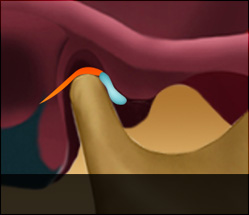

정상디스크 위치

입을 다물고 있는 상태

입을 열고 있는 상태

정상 디스크 위치